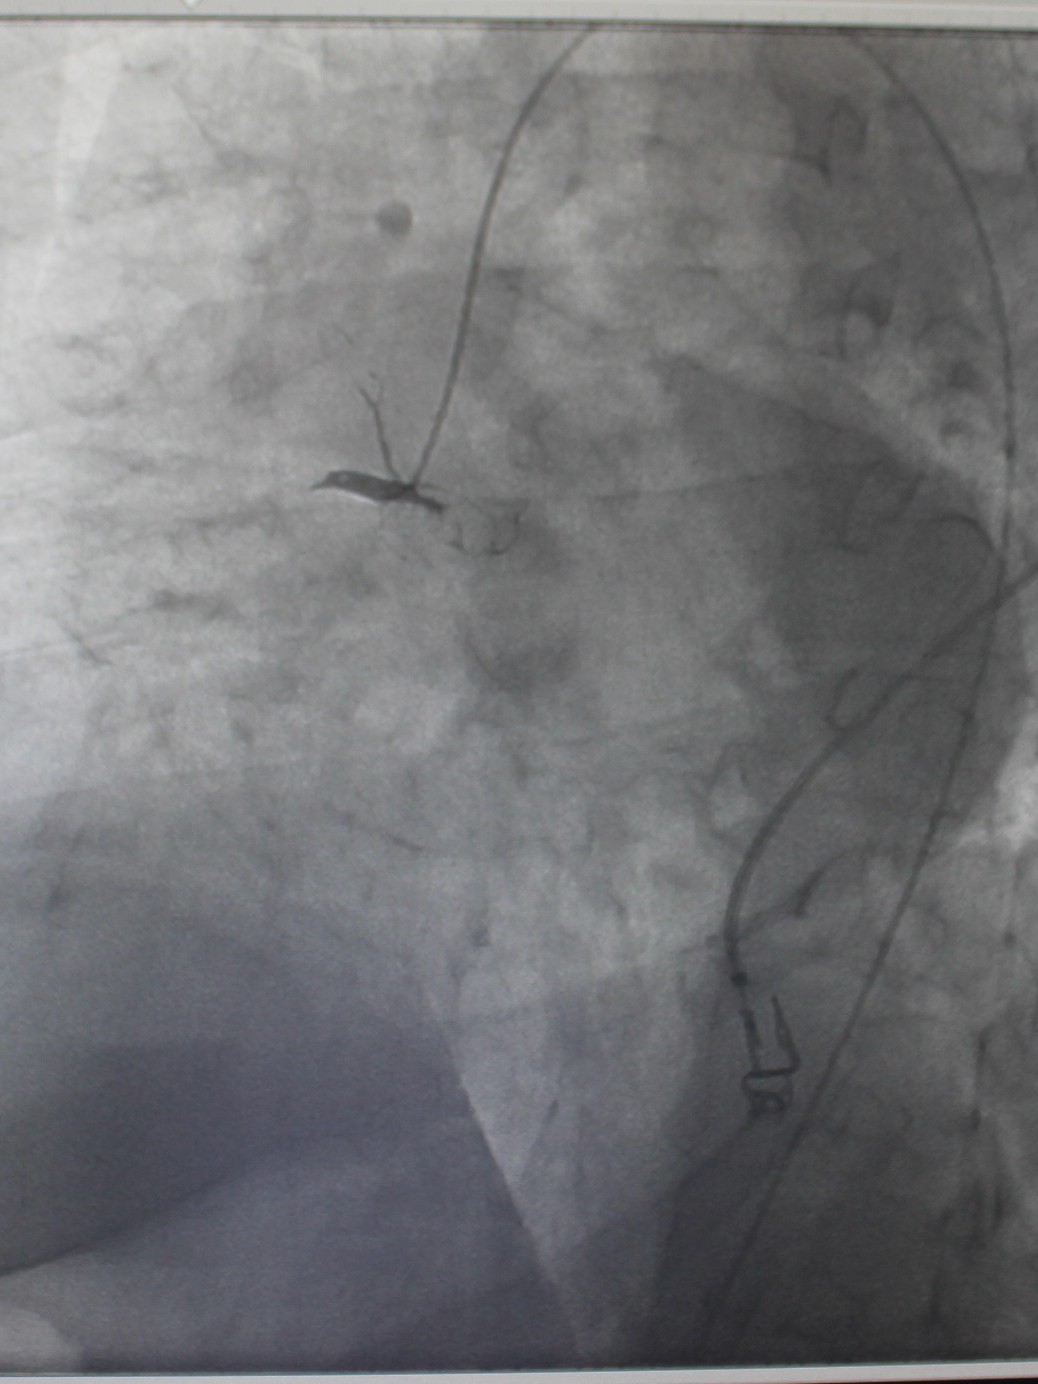

По экстренным показаниям проведена коронароангиография, выявлено стенозирующее многососудистое поражение: стеноз (сужение) передней межжелудочковой ветви левой коронарной артерии 80% в проксимальной трети, стеноз огибающей ветви 75% в дистальной трети (при том, что существенным рассматривают сужение артерии > 50%), тромботическая окклюзия правой коронарной артерии (в проксимальной трети). Рентгенхирурги выполнили тромбэкстракцию из правой коронарной артерии, баллонную ангиопластику со стентированием правой коронарной артерии (2 стента с лекарственным покрытием). Операция продолжалась около часа, после чего пациент продолжил лечение под наблюдением врачей отделения кардиореанимации; через двое суток был переведен в отделение кардиологии для дальнейшего лечения.

| Окклюзия правой коронарной артерии, кровоток отсутствует | Аспирационным катетером выполнена механическая тромбэкстракция |

| Обнаружены участки стенозирования артерии | Установлены 2 стента, стенты раскрыты | На контрольной ангиограмме: коронарный кровоток восстановлен, раскрытие стентов полное, позиционирование адекватное |